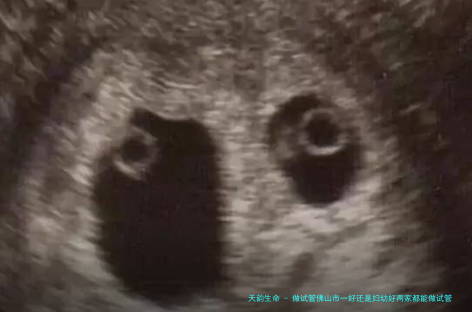

做试管佛山市一好还是妇幼好两家都能做试管婴儿,在佛山市,选择做试管婴儿的医院时,佛山市第一助孕医院和佛山市生育保健院是2个常见的选择。两家医院都具备先进的设备和技术,并且在生殖医学范围享有丰富的经验。为了协助您更佳地认识这两家医院的特点,以下将从多个方面进行比较,以供对照。

做试管佛山市一好还是妇幼好两家都能做试管婴儿。注:数据来源网络,具体请依当地医院为准。